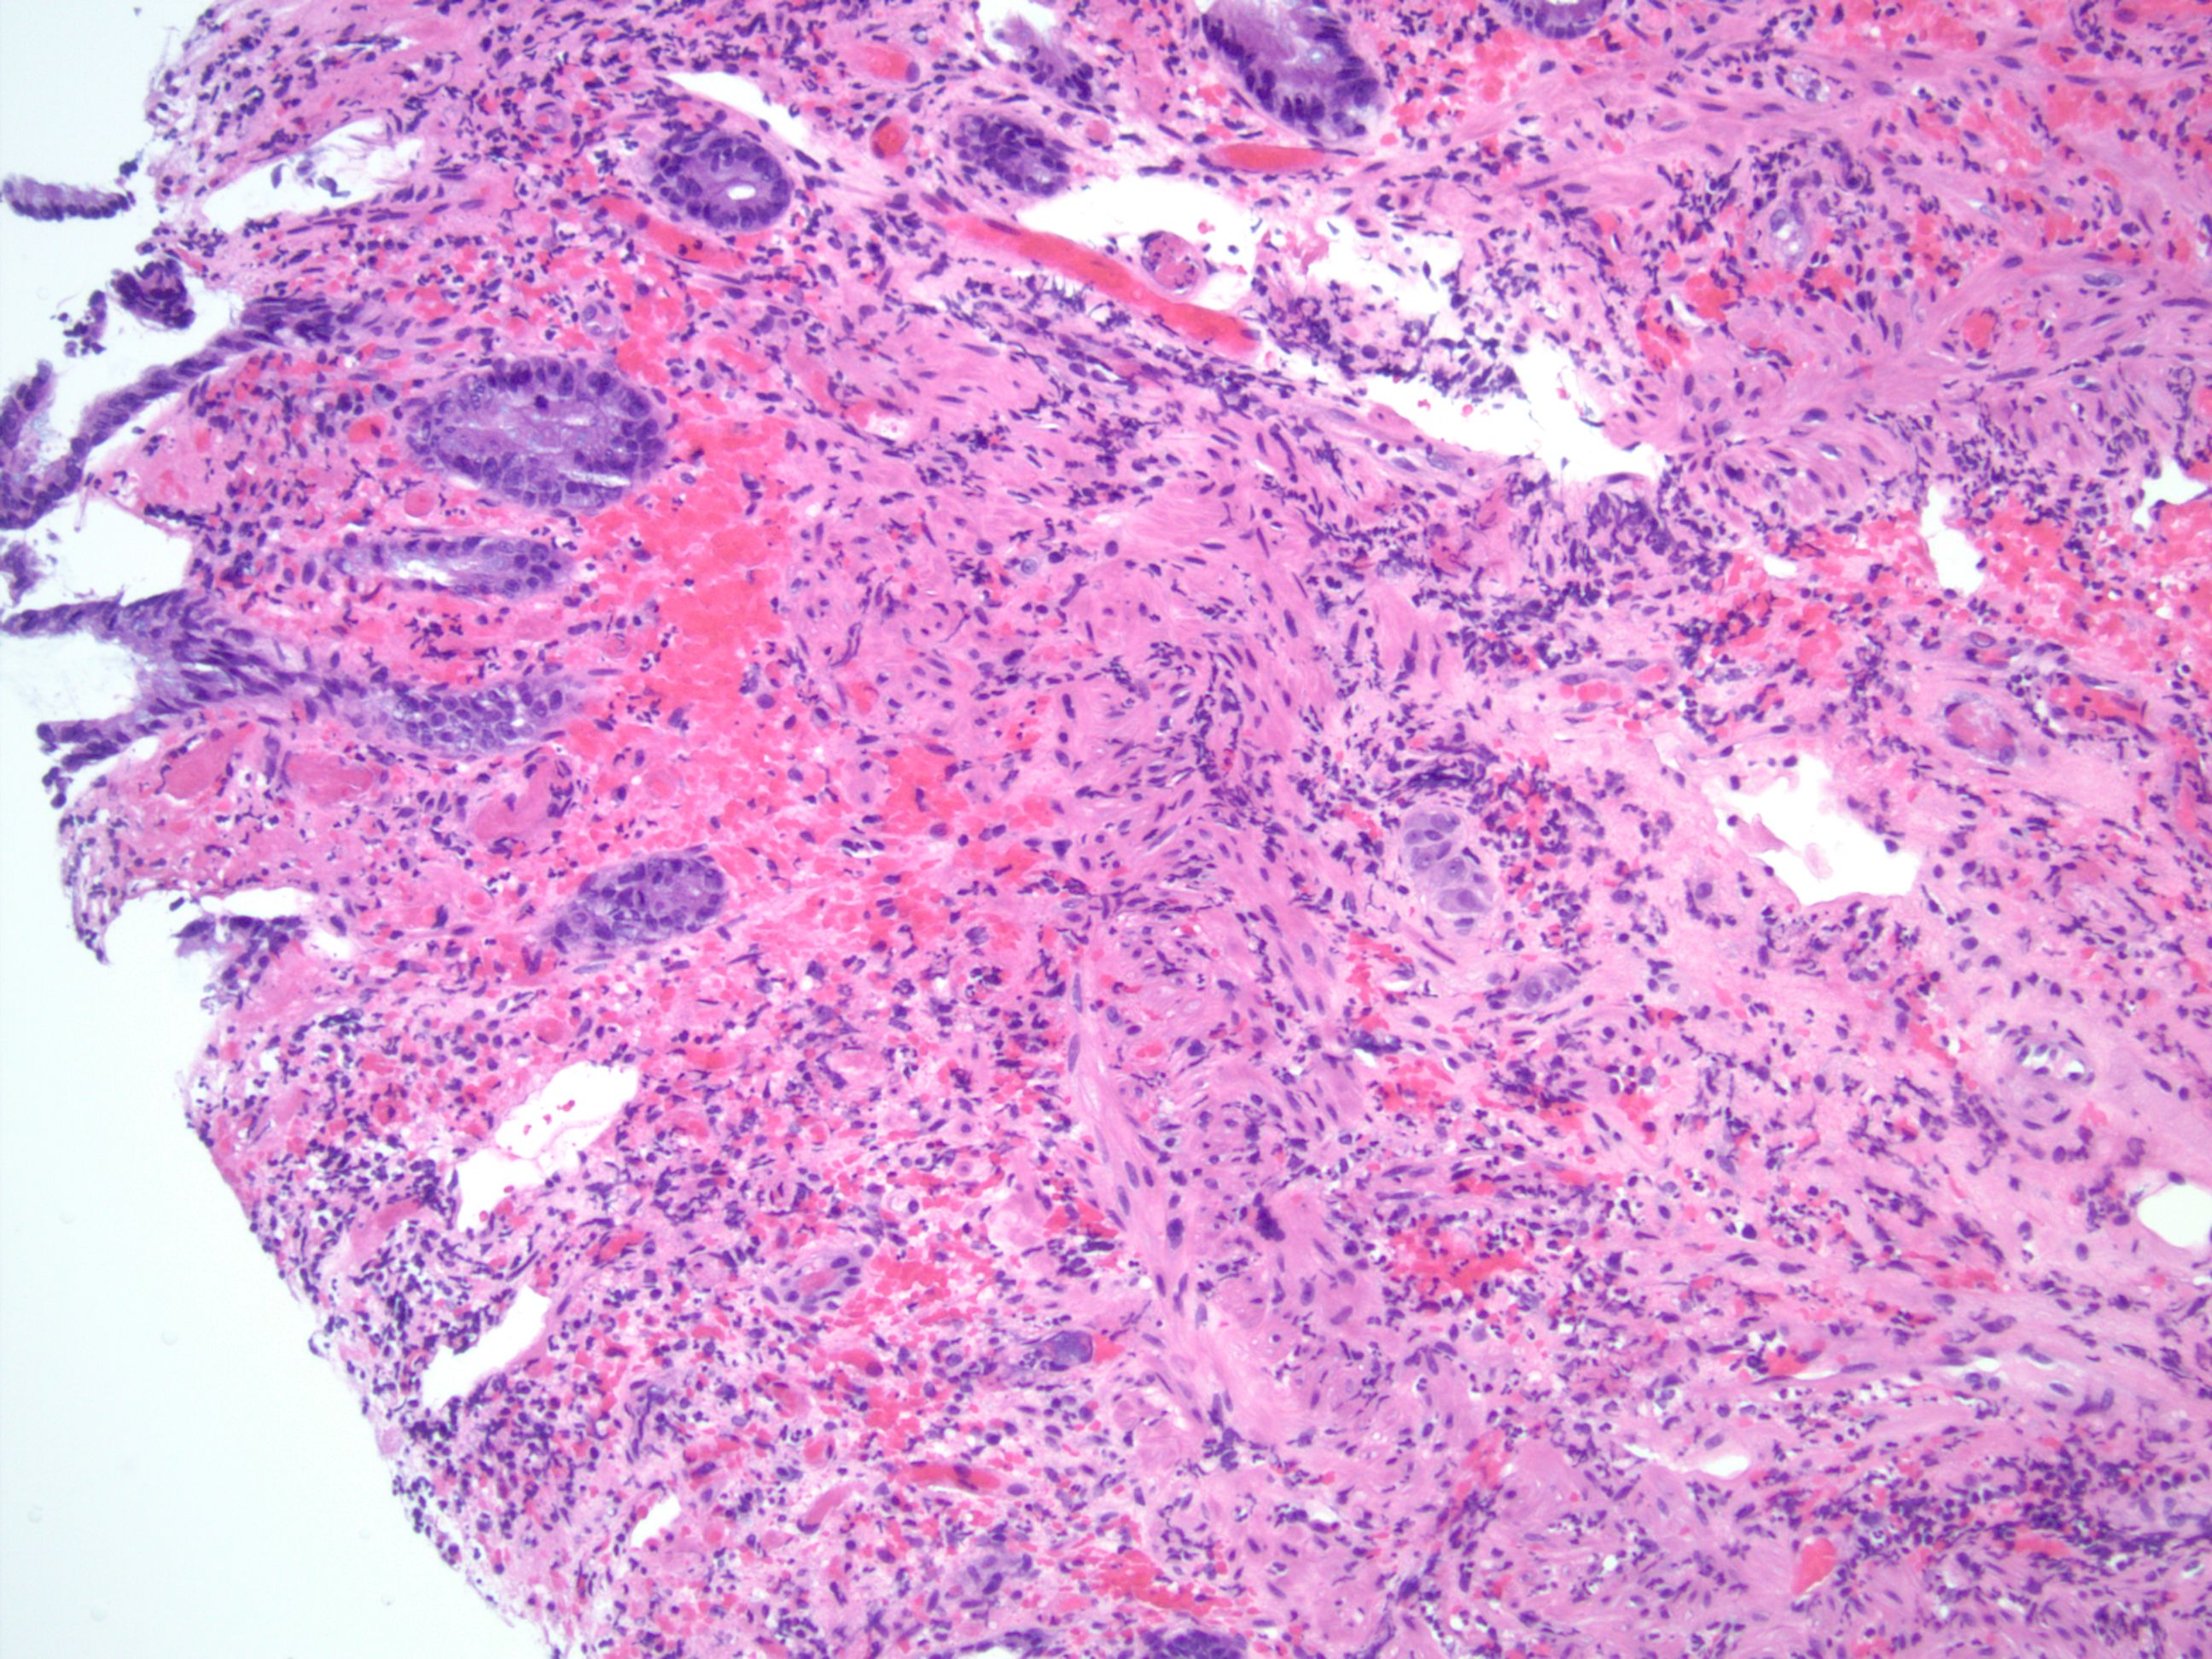

早期黏膜表面溶解,仅隐窝底部完整。隐窝底部表现萎缩,可显示显著再生性的不典型性,炎症较少。

固有层玻璃样变,三色染色显示蓝色。黏膜下显著水肿,黏膜肌层斜面分裂(或许由于水肿),假膜形成。

随着疾病的进展,可出现克罗恩病样改变,但吞噬含铁血黄素巨噬细胞的出现支持缺血,炎症增多伴隐窝变形,溃疡愈合的区域可见伴食物颗粒的巨细胞,不能与克罗恩肉芽肿混淆。常查找血管是否存在血栓栓塞性疾病或血管炎,常位于手术切除的标本或患者的肠系膜内,内镜活检的标本几乎不见血管炎的证据,不能过度解读溃疡床血管的血栓及炎症为血栓栓塞性疾病或血管炎。